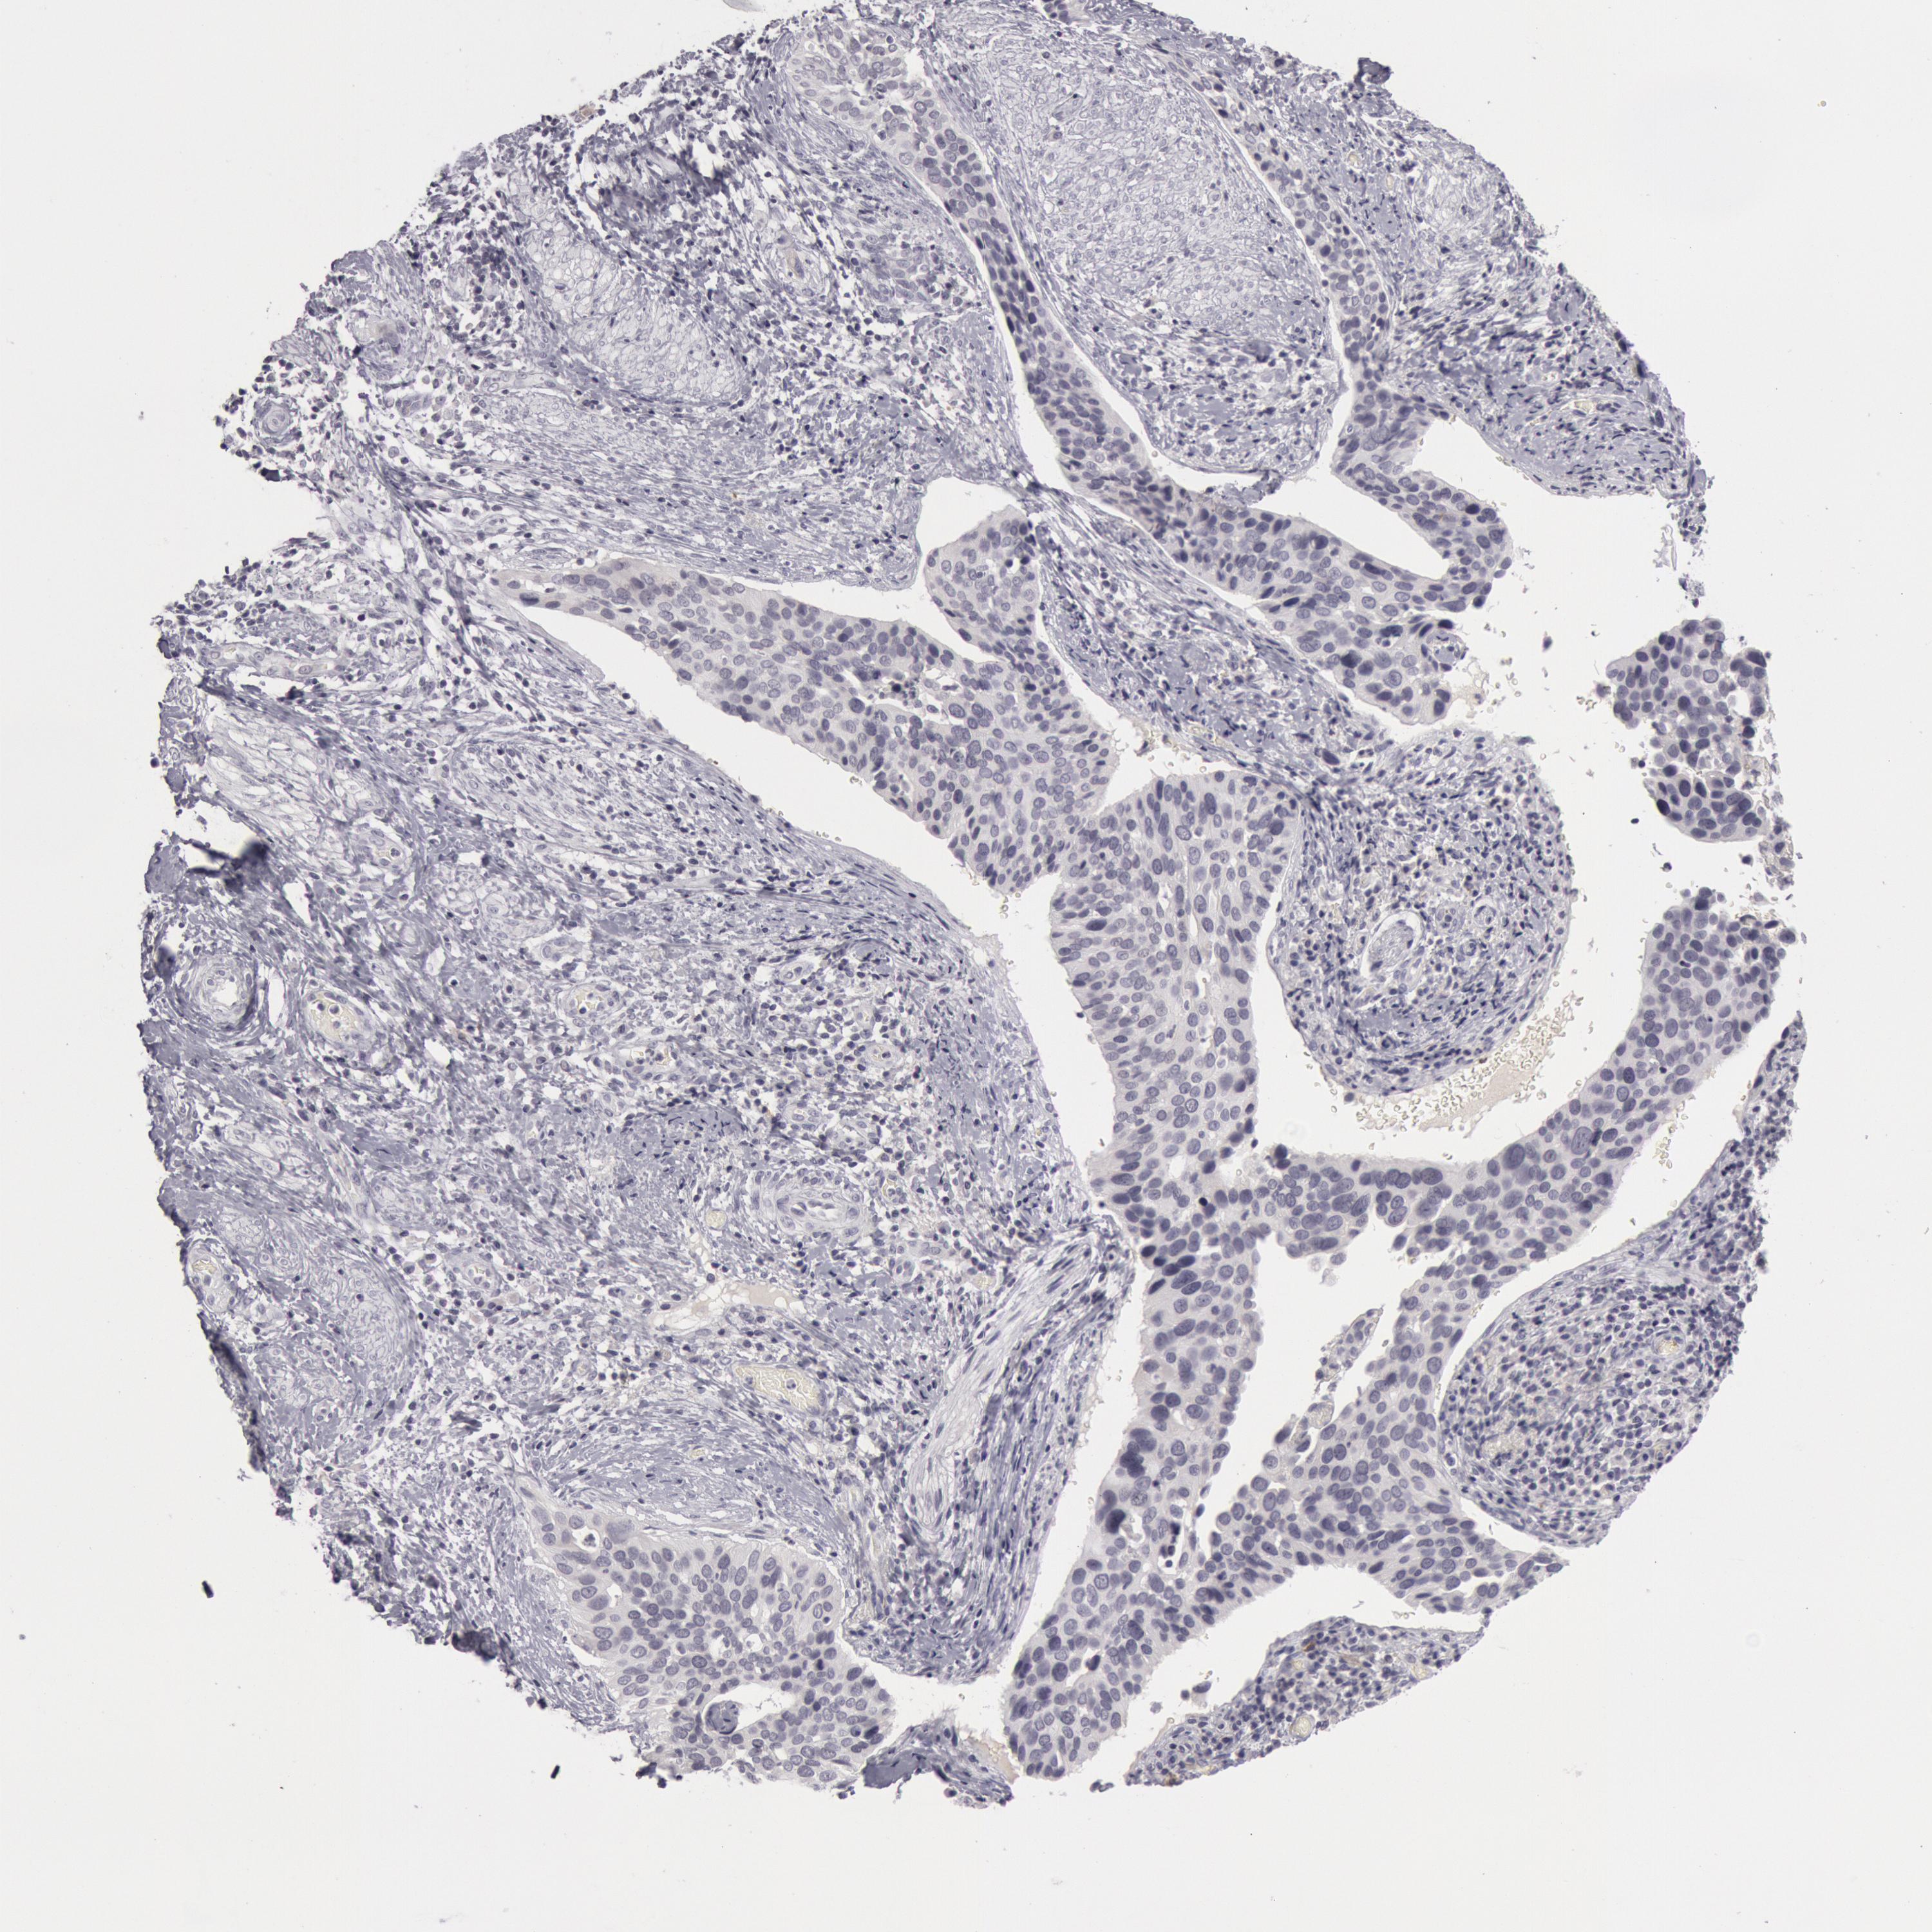

CERVICAL CANCER - Protein expressioni

A mouse-over function shows sample information and annotation data. Click on an image to view it in a full screen mode. Samples can be filtered based on level of antibody staining by selecting one or several of the following categories: high, medium, low and not detected. The assay and annotation is described here.

Note that samples used for immunohistochemistry by the Human Protein Atlas do not correspond to samples in the TCGA dataset.

Antibody stainingi

Antibody staining in the annotated cell types in the current human tissue is reported as not detected, low, medium, or high, based on conventional immunohistochemistry profiling in selected tissues. This score is based on the combination of the staining intensity and fraction of stained cells.

Each image is clickable and will lead to virtual microscopy that enables deeper exploration of all samples and also displays staining intensity scores, fraction scores and subcellular localization as well as patient and tissue information for each sample.

Antibody CAB000136

Staining

High

Medium

Low

Not detected

Intensity

Strong

Moderate

Weak

Negative

Quantity

>75%

75%-25%

<25%

None

Location

Nuclear

Cytoplasmic/membranous

Cytoplasmic/membranous,nuclear

Adenocarcinoma, NOS

Squamous cell carcinoma, NOS